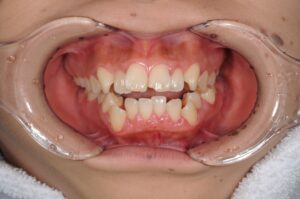

まずは初診時の写真を見て下さい。

【初診時】